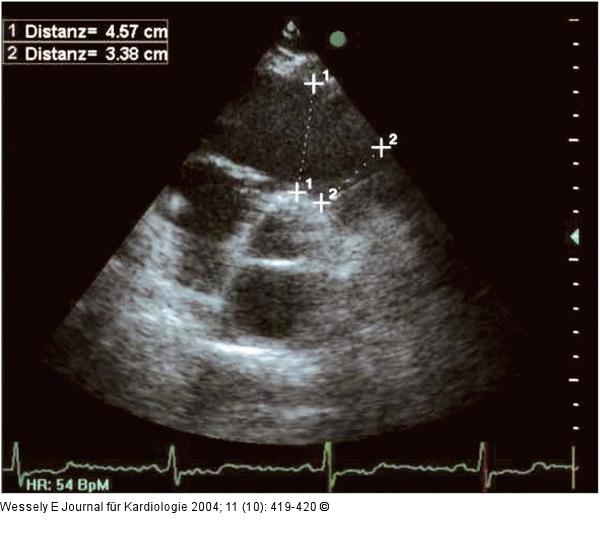

Abbildung 5: Parasternaler Längsschnitt - Parasternaler Querschnitt Parasternaler Längs- und Querschnitt mit Vermessung des rechtsventrikulären Ausflußtraktes in mehreren Ebenen. |

Parasternaler Längs- und Querschnitt mit Vermessung des rechtsventrikulären Ausflußtraktes in mehreren Ebenen. |